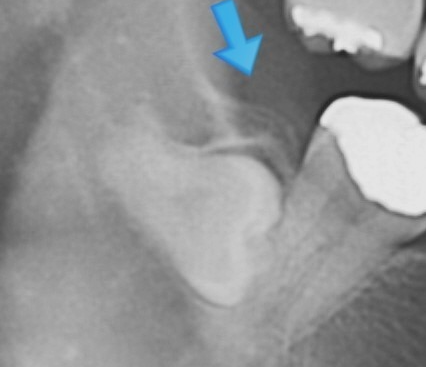

완전 매복 발치 : 36,600 ~ 37,900원 (2022년 일반 의원급 기준)

치아머리 부분이 치조골에 2/3 이상 매복된 상태로 치조골 삭제 및 치아 분할 술을 같이했을 경우입니다.